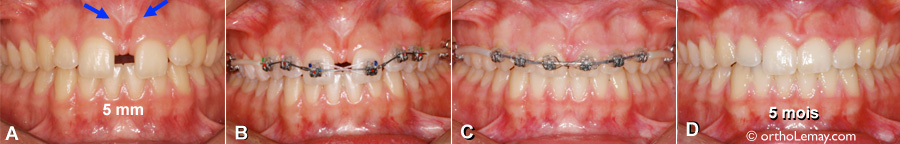

Fermeture d’un diastème de 5 mm en 5 mois

• (A) Une frénectomie labiale avait été faite auparavant dans l’espoir que le diastème se referme, ce qui était impossible et n’a rien donné comme résultat.

• (B) Pose des appareils fixes multi-bagues.

• (C) Après 5 mois de corrections orthodontiques.

• (D) Après l’enlèvement des appareils et qu’une gingivectomie ait été faite entre les incisives centrales.